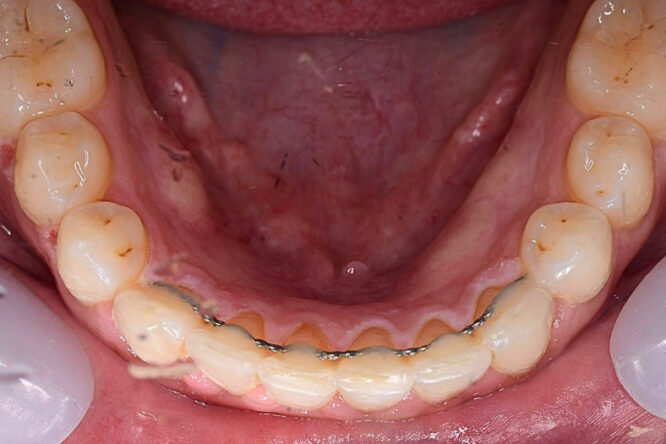

Before

Case 7 – Orthodontics